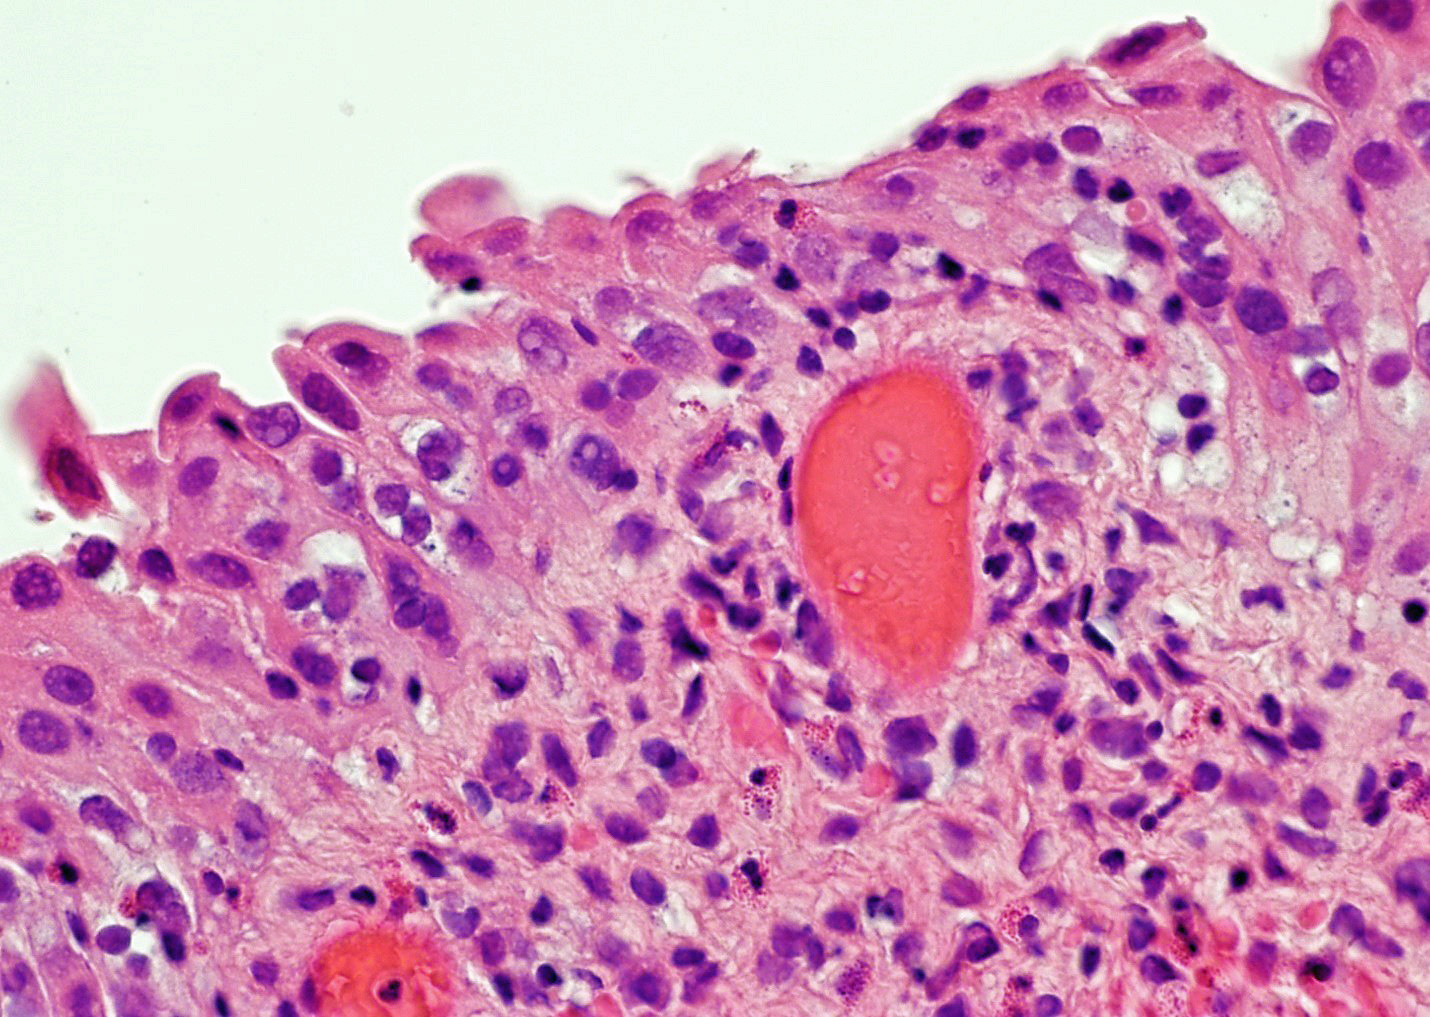

- Vessels with fibrin thrombi, fibrinoid vascular necrosis, vascular congestion, thickened walls, endothelial proliferation and telangiectasia

- Urothelium can show

- Nuclei with variation in nuclear size and shape, hyperchromasia, vesicular or smudgy chromatin

- Eosinophilic or amphophilic cytoplasm, cytoplasmic vacuoles

- Multinucleated giant cells (Am J Surg Pathol 2008;32:92)

- Usually no mitotic figures

- Surface erosion, ulceration

- Squamous metaplasia

- Pseudocarcinomatous urothelial hyperplasia: variable sized urothelial cords and nests with rounded or irregular edges present in the lamina propria and enclose dilated blood vessels with fibrin deposition (Am J Surg Pathol 2008;32:92)

- Acute phase: edematous, congested and telangiectatic vessels, acute and chronic inflammatory infiltrate, atypical stromal cells with multinucleated forms

Microscopic (histologic) images

Contributed by Y. Albert Yeh, M.D., Ph.D. and Jennifer Lee, M.D.